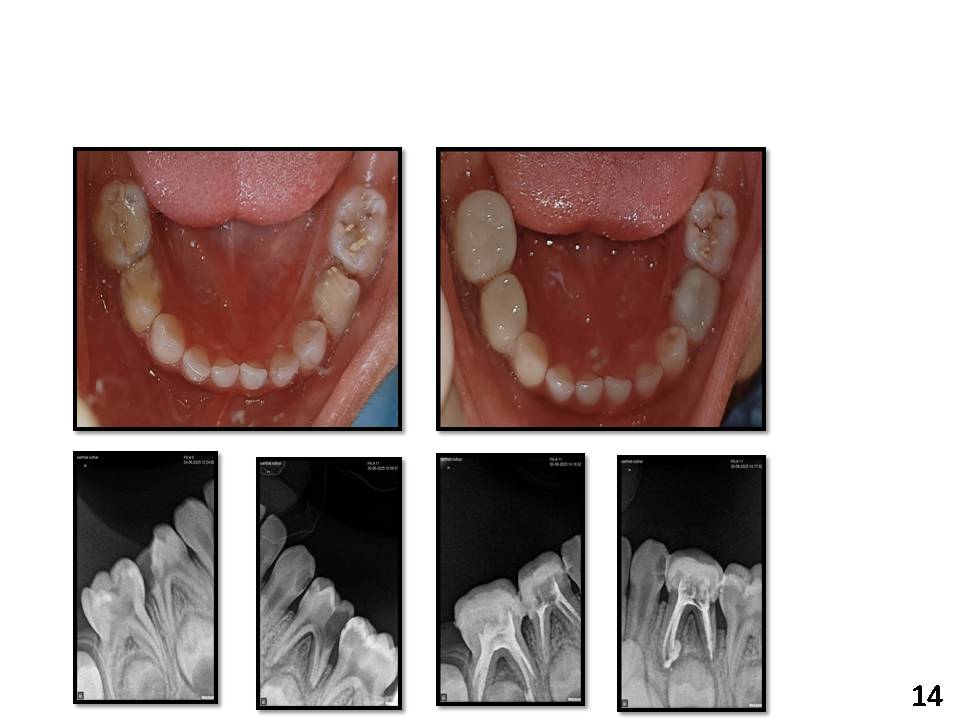

Cases

A new era of Pedocrown